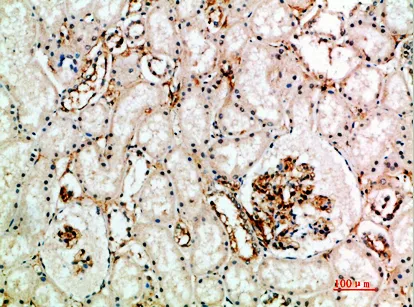

CD63 Rabbit Polyclonal Antibody

Cat: APRab08430

Size1:50μl Price1:$118

Size2:100μl Price2:$220

Size3:500μl Price3:$980

Size2:100μl Price2:$220

Size3:500μl Price3:$980